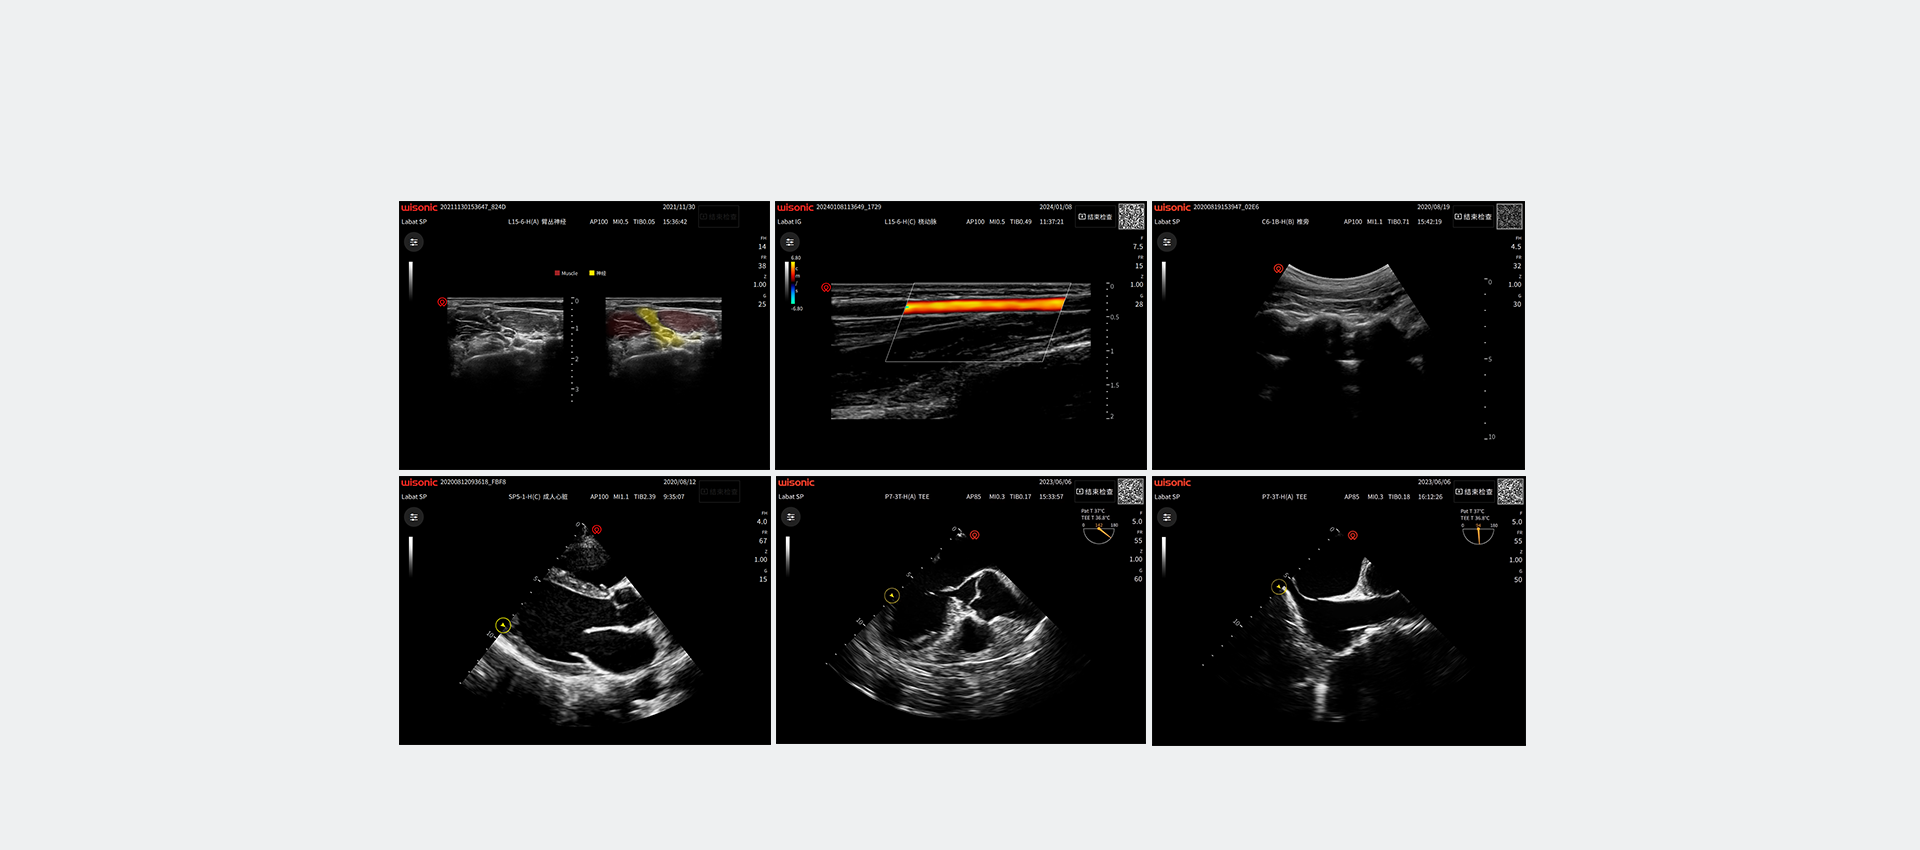

Application pictures